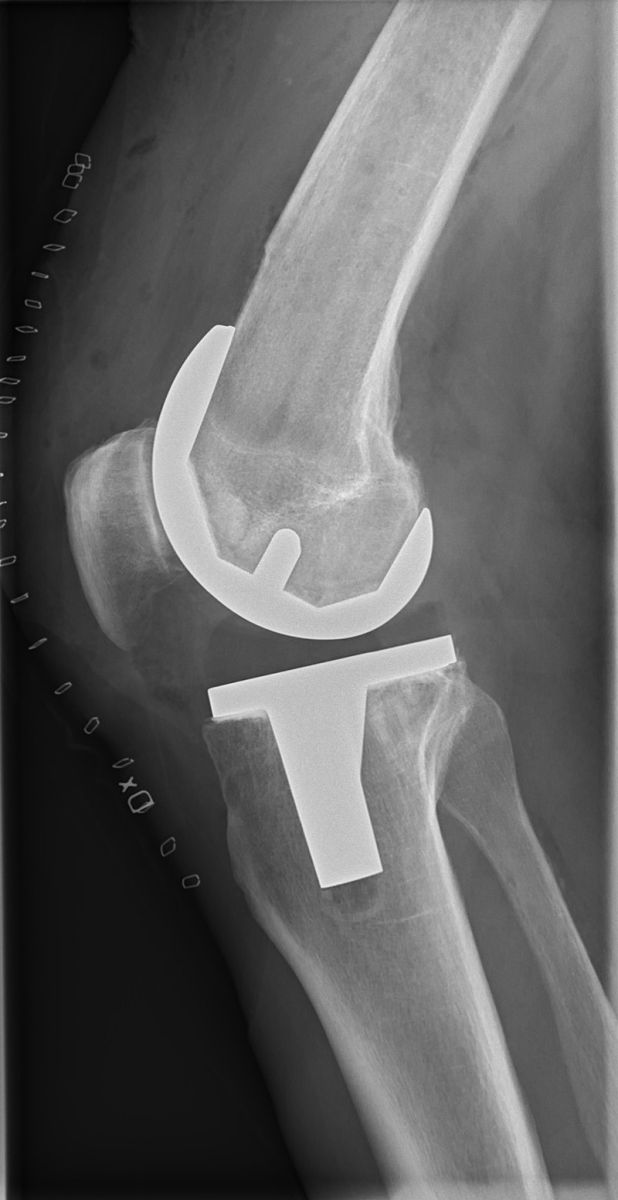

Diz protezi ameliyatında bölgesel ya da genel anestezi kullanılır. Bölgesel anestezide hasta uyanıktır ve belden aşağısını ameliyat boyunca hissetmez. Genel anestezide ise hastanın bilinci tamamen kapalıdır. Cerrahi işlem genellikle 1 ila 1,5 saat kadar sürer. Ameliyatta hasarlı kıkırdak ve kemik çıkarılır ve ardından yeni metal ve plastik implantlar dizin hizasını ve işlevini eski haline getirecek şekilde yerleştirilir.

Diz protezi yapılmış hastanın iki yönlü grafisi